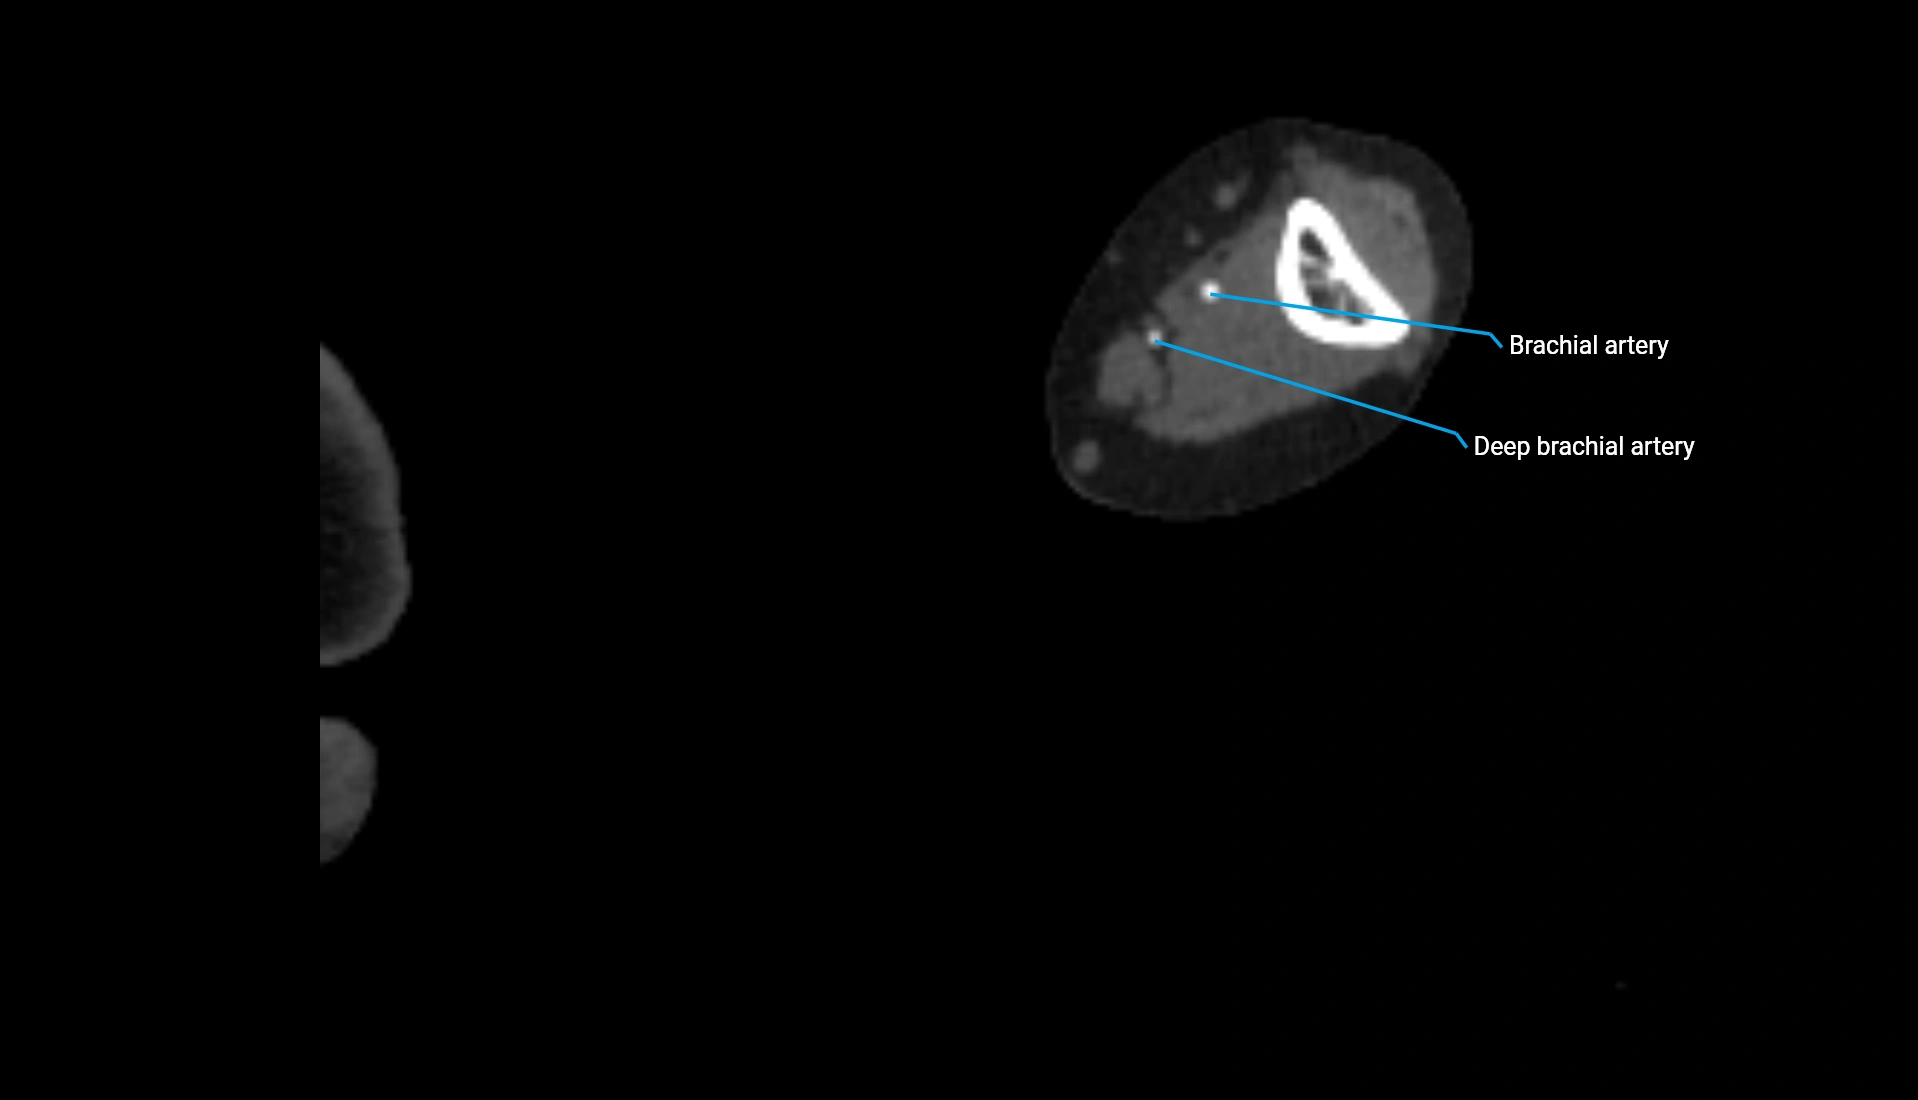

CT Appearance

Non-Contrast CT:

• Cortex: High-density, sharply defined

• Subchondral bone: Dense cancellous matrix

• Articular surface: Smooth concave contour articulating with the capitellum

• Excellent for evaluating bone integrity, alignment, and subtle fractures

Post-Contrast CT:

• Bone: No enhancement

• Joint capsule and synovium: Mild enhancement outlining the joint

• Improves contrast between soft tissues and bony margins

• Useful in detecting subtle joint abnormalities or postoperative changes